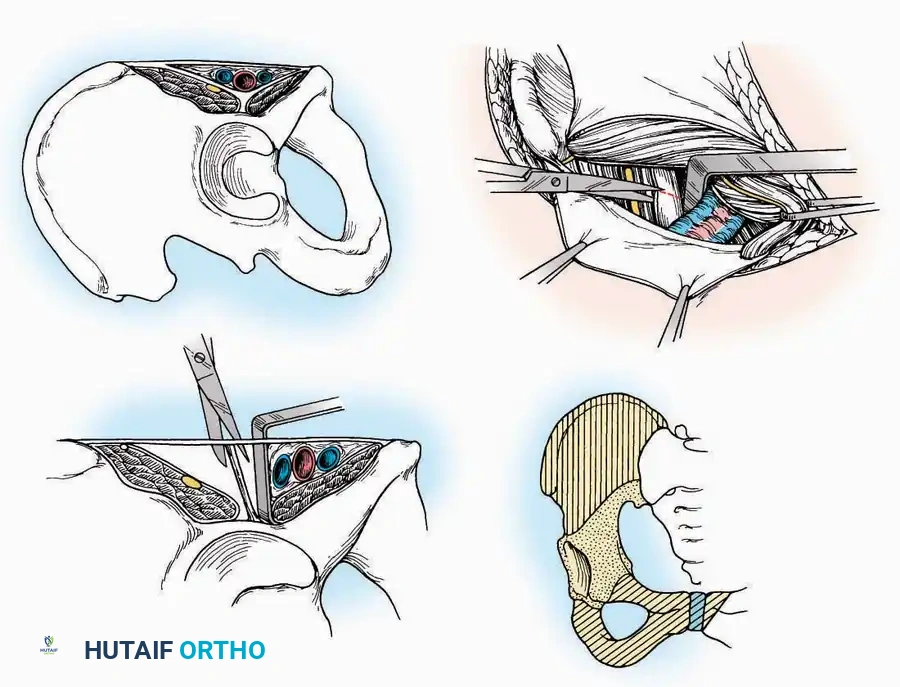

Anterolateral Approach

The anterolateral approach is widely considered the "universal incision" for the foot and ankle. It provides unparalleled access to the ankle joint, the talus, and the majority of the tarsal articulations, while safely avoiding the major anterior neurovascular bundle. The only tarsal joints inaccessible via this route are the naviculocuneiform joints (specifically the medial and intermediate).

Indications: Total talectomy, triple arthrodesis, ankle arthrodesis, and open reduction of complex talar neck fractures.

Surgical Technique:

* Incision: Begin over the anterolateral aspect of the leg, medial to the fibula and 5 cm proximal to the ankle joint line. Carry it distally over the joint, crossing the anterolateral aspect of the talar body and the calcaneocuboid joint, terminating at the base of the fourth metatarsal.

* Superficial Dissection: Incise the superficial fascia and the superior and inferior extensor retinacula down to the periosteum of the tibia and the ankle joint capsule.

* Vascular Ligation: This trajectory usually requires the identification and ligation of the anterolateral malleolar and lateral tarsal arteries.

* Nerve Protection: Retract the skin edges carefully. Identify and protect the intermediate dorsal cutaneous branches of the superficial peroneal nerve (SPN), which frequently cross the distal aspect of this incision.

* Muscle Management: Identify the origin of the extensor digitorum brevis (EDB) muscle on the lateral calcaneus. Divide it in the direction of its fibers, or detach its origin entirely and reflect it distally to expose the subtalar and calcaneocuboid joints.

* Deep Exposure: Retract the extensor digitorum longus (EDL) tendons, the dorsalis pedis artery, and the deep peroneal nerve (DPN) medially. Incise the anterior ankle capsule to expose the tibiotalar joint.

* Tarsal Exposure: Expose the talonavicular joint by dissecting deep to the extensor tendons and incising its capsule transversely. Continue laterally through the capsule of the calcaneocuboid joint. By excising the fat pad within the sinus tarsi (lateral and inferior to the talar neck), the posterior facet of the subtalar joint is brought into direct view.